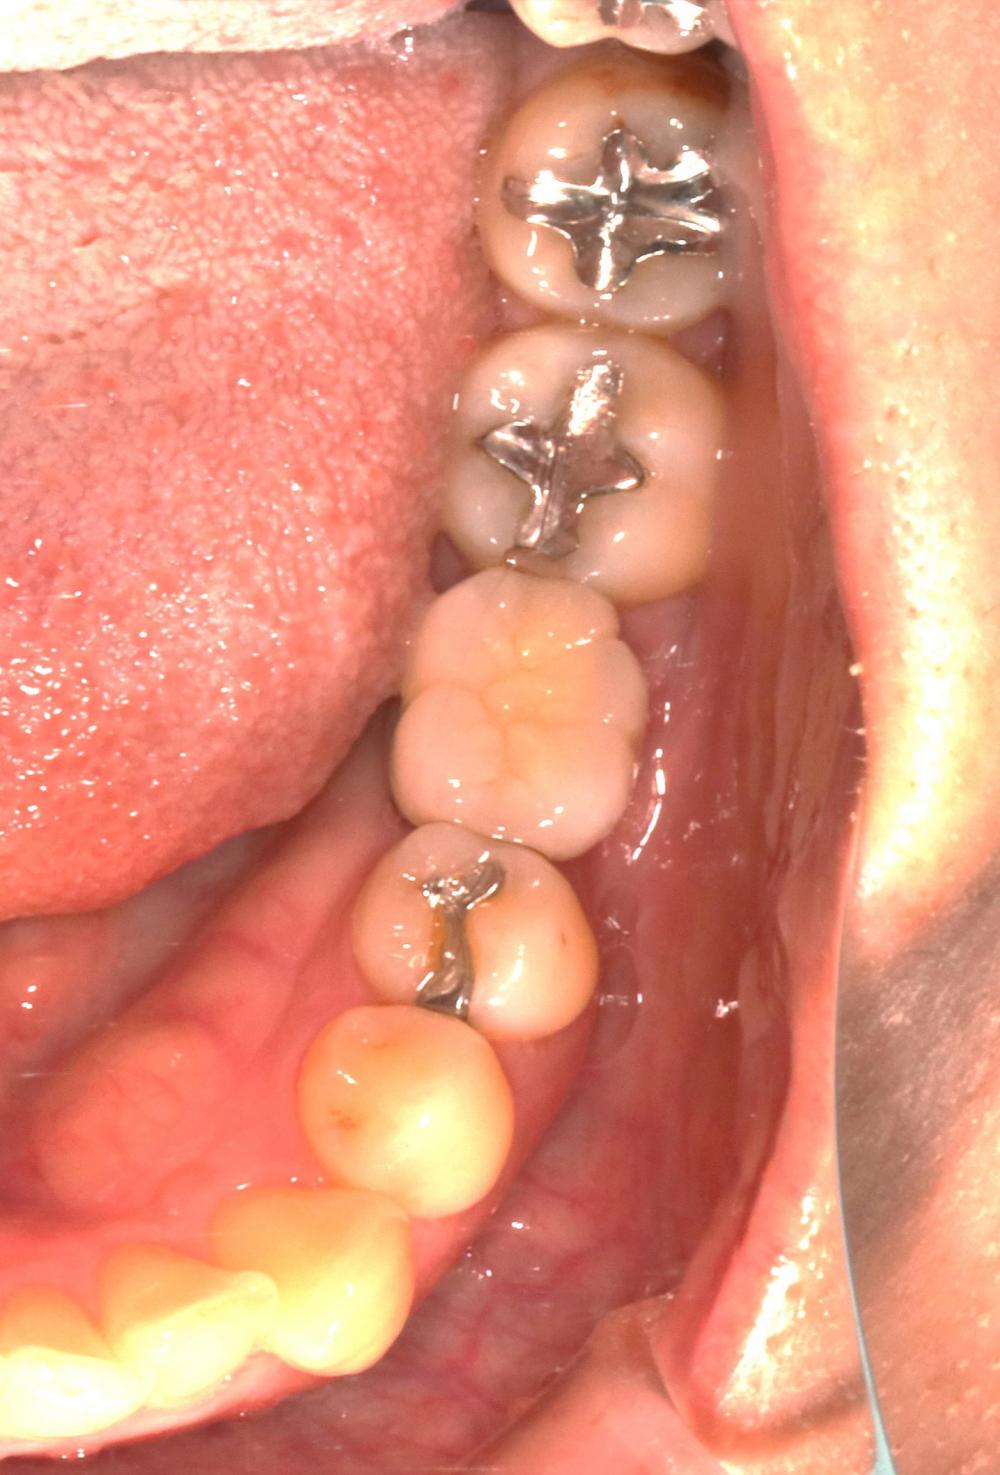

2024.08.1750代女性「歯科恐怖症で治療ができなかった。歯がボロボロで噛めない」インプラントとメタルボンドを入れ、物が噛めてご飯が食べられるようになった症例